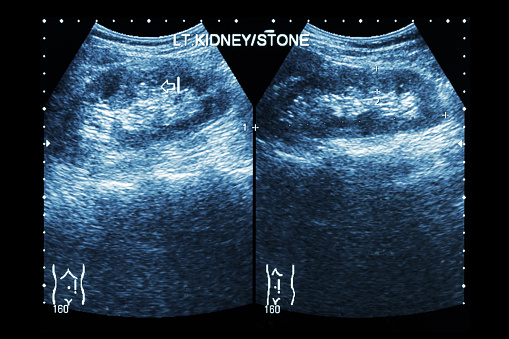

Enlarged prostate treatment may help passage of large kidney stones in the urine

Enlarged prostate treatment may help with the passage of large kidney stones in the urine. The patients in the study were treated with tamsulosin, a common treatment for an enlarged prostate. The researchers found this treatment helped improve kidney stone passage through urine. Researcher Dr. Jeremy Furyk explained, “Kidney stones are a bit of a ...click here to read more